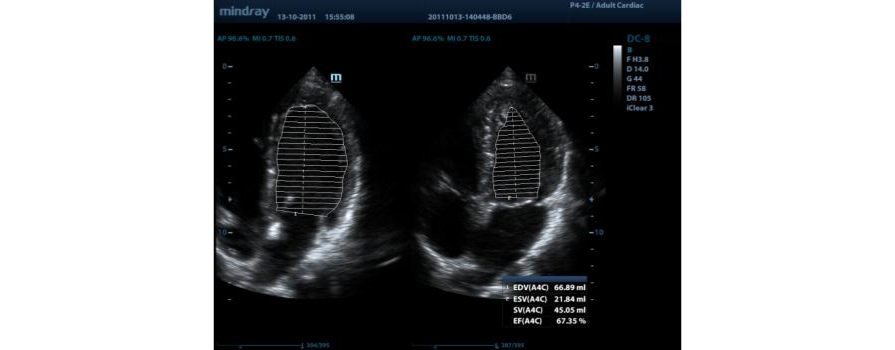

AutoEF

Automatic recognition of the diastole and systole from 2D echo clips and output EDV/ESV/EF etc. results using the Simpson method.?

?